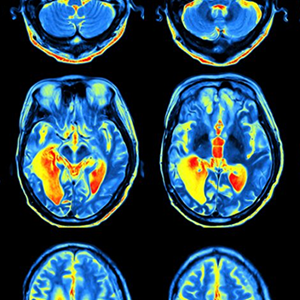

Visión Computacional aplicada a Salud

- Visión Computacional aplicada a la salud

- Visión Computacional – Computer Vision